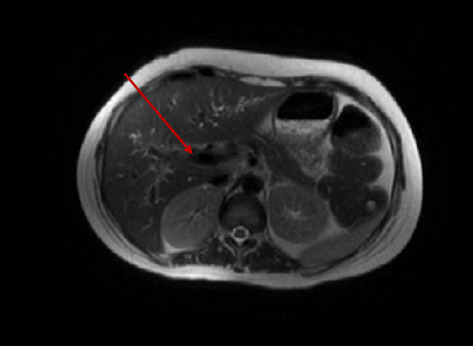

Human T-lymphotropic virus type 1 (HTLV-1), the first oncogenic retrovirus discovered in humans, is primarily associated with two disease entities: adult T cell leukemia-lymphoma and HTLV-1-associated myelopathy-tropical spastic paresis. HTLV-1 has also been implicated in the pathogenesis of various autoimmune rheumatic diseases, and its association with the autoimmune disorders of the gastrointestinal track is less well understood. Our patient, a 26-year-old previously healthy female, presented with recurrent, progressively worsening chronic abdominal pain and persistent liver test abnormalities. Initially diagnosed with acute acalculous cholecystitis and autoimmune hepatitis (AIH), her liver tests continued to exhibit a predominantly cholestatic pattern. This prompted further advanced imaging, and magnetic resonance cholangiopancreatography ultimately confirmed a diagnosis of primary sclerosing cholangitis (PSC). Complicating her condition further, she developed lower extremity weakness, initially attributed to axonal Guillain-Barré syndrome, which unfortunately did not respond to standard treatment. After a year marked by progressive clinical decline with repeated and prolonged hospitalizations due to fever of unknown origin, an extensive diagnostic workup ultimately led to a diagnosis of HTLV-1 myelopathy, along with AIH-PSC overlap syndrome. This case highlights the diagnostic challenges associated with the multisystem involvement of HTLV-1. Notably, our patient's presentation was not consistent with classic HTLV-1 myelopathy rather a subtype with rapidly progressive symptoms and flaccid as opposed to spastic paresis. The association between HTLV-1 infection and autoimmune cholangiopathy is exceptionally rare. To the best of our knowledge, our case represents only the second reported instance of autoimmune cholangiopathy associated with HTLV-1 myelopathy and the first reported case of AIH-PSC overlap syndrome associated with HTLV-1 myelopathy. This underscores the need for heightened clinical awareness of potential hepatic immune manifestations in patients with HTLV-1 infection, even in the absence of classic neurologic symptoms at initial presentation.